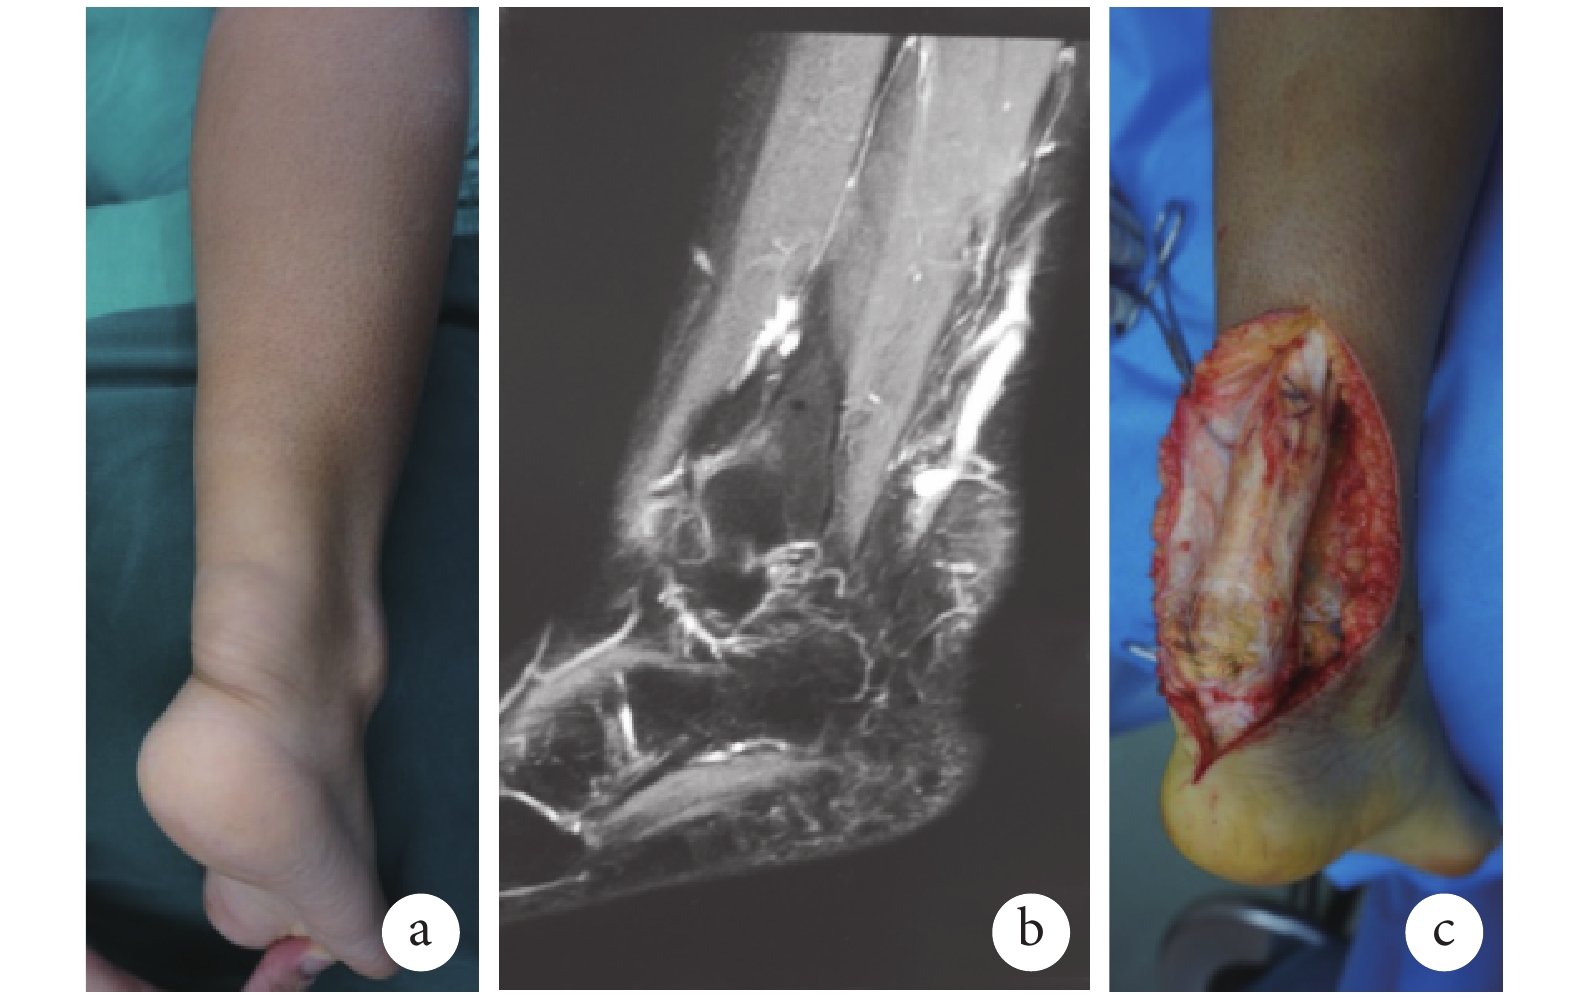

患者 女,38 歲。因發現雙足跟部腫物 16 年,疼痛伴活動受限 2 年入院。檢查:雙跟腱處可觸及大小約 9 cm×3 cm×1 cm 腫物,邊界清,質韌、可隨跟腱屈伸活動,無壓痛,腫物表面皮膚完整、無破潰、無色素沉著(圖 1a),美國矯形足踝協會(AOFAS)踝與后足評分為 58 分。雙側跟腱 MRI 示:雙側跟腱呈梭形膨大,信號不均勻(圖 1b)。此外,患者存在神經系統癥狀,包括雙側膝、腱反射亢進,Hoffmann 征陽性,Babinski 征陽性,指鼻輪替差,走路不穩,回答問題遲鈍。頭部 MRI 檢查示:雙側額葉、放射冠、側腦室前后角旁可見多發斑片狀等長或稍長 T1 及長 T2 異常信號。生化檢查示:膽固醇濃度正常,膽甾烷醇濃度約為正常濃度的 3 倍。入院診斷:腦腱黃瘤病。家族中妹妹雙足跟部腫物 10 年、無神經系統癥狀。

于全麻下行雙側跟腱腫瘤切除、?長屈肌腱轉移重建跟腱術。術中探查見雙側跟腱自腱腹移行處起至止點處膨大呈梭形、黃褐色,界限清,跖肌及深層肌未受累(圖 1c)。完整切除腫物后,左、右側跟腱缺損長度分別為 10.0、9.5 cm。游離?長屈肌腱并于 Henry 結節處切斷,然后轉移至原跟腱位置,在跟骨結節處鉆一直徑約 4.5 mm 橫行骨孔,于踝關節跖屈約 15° 位將?長屈肌腱穿骨孔并將遠端反折與自身縫合。術后病理檢查示雙跟腱送檢腫物呈黃色瘤樣改變。術后石膏固定踝關節于跖屈 15° 位 6 周,去除石膏后開始踝關節非負重活動度鍛煉,8 周后逐漸負重并練習下蹲、提踵等動作。術后 1 年,患者行走功能恢復可,下蹲正常,單足提踵肌力 M4,AOFAS 踝與后足評分為 96 分。但因患者未接受神經內科治療,神經系統癥狀較 1 年前加重。

患者術前及術中檢查 a. 術前踝部腫物外觀;b. 術前 MRI;c. 術中跟腱外觀